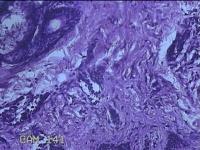

性别

男

年龄

23岁

临床诊断

右耳部肿物

一般病史

右耳前无痛性肿物20余年。

标本名称

大体所见

灰白暗红色肿物0.7x1.5x0.2cm一个,表面糜烂。

图2